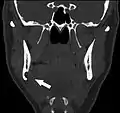

Stafne bone cavity seen on coronal CT

Stafne bone cavity seen on axial CT